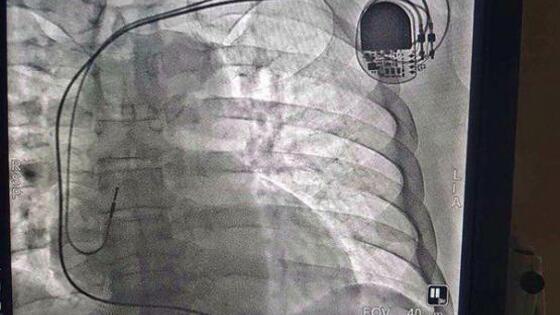

В центральной городской больнице впервые в нашем округе была сделана имплантация двухкамерного стимулятора. Как рассказал КС заведующий отделением рентгенохирургических методов диагностики и лечения ЦГБ Игорь Чиканов, это была экстренная операция, в ней нуждался пациент 59 лет с диагнозом «атриовентрикулярная блокада третей степени». У больного были проблемы с сердечным ритмом, стимулятор позволит его регулировать. Ранее пациентов с такими патологиями отправляли на лечение в другие регионы страны. – На Ямале больше сотни таких пациентов, – отметил Игорь Анатольевич. – Наша больница будет развивать это направление. Сейчас прооперированный больной находится в общей палате, через два-три дня мы его выпишем.